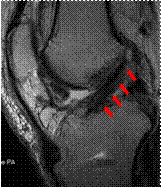

腱を移植するために長方形に作成した骨孔

現在スポーツ愛好者は、若年者のみでなく、中高年、高齢者にまで広がっています。一方で、スポーツによる障害や外傷の発生率も増加しております。我々は、スポーツで生じた膝前十字靭帯損傷や膝半月板損傷、外傷性肩関節脱臼や肩腱板断裂に対し、内視鏡を用いた手術を積極的に行っております。

もちろん、目標は日常生活復帰だけではなく、スポーツ復帰・職場復帰です。関節鏡を用いているため、体の負担も少なく、早期の復帰を目指せます。

再建された膝前十字靱帯